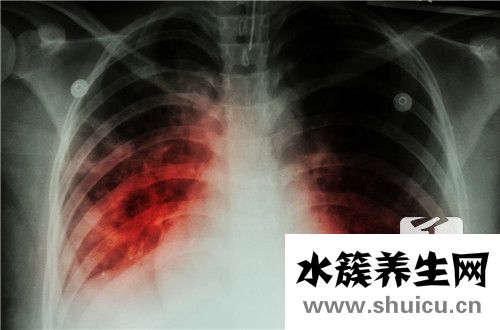

雙側胸膜增厚有很多原因,那么什么是雙側胸膜增厚呢?事實上,兩側胸膜增厚可能是由肺炎和肺結核引起的。肺炎患者必須記住不要拖延時間。他們必須及時接受常規治療,同時有合理的飲食。因此,讓我們分享一些適合肺炎患者的食物。